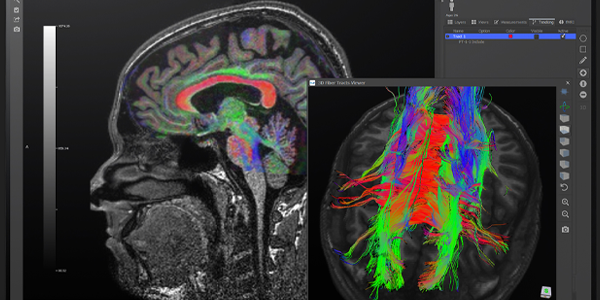

• Difüzyon Tensör Görüntüleme (DTI): DTI, su moleküllerinin hareket yönünü ve derecesini ölçerek beyindeki sinir lif yollarının haritasını çıkarır. Bu yöntem, beyin bağlantılarını değerlendirmek ve travmatik beyin hasarı, inme ve diğer nörolojik hastalıkların teşhisinde kullanılabilir. Ayrıca, beyin cerrahisi öncesinde planlama yapmak ve kritik beyin bölgelerinden kaçınmak için de kullanılabilir.

• Traktografi: DTI verilerini kullanarak beyindeki sinir lif yollarının üç boyutlu görüntülerini oluşturur. Bu yöntem, beyin bağlantılarını daha iyi anlamak ve cerrahi planlama için kullanılabilir.